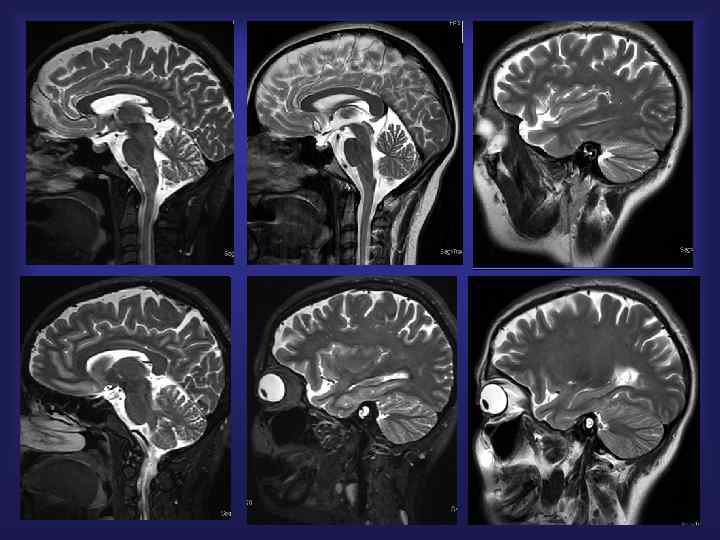

МРТ 1. 5 Тесла Т 2 -23 среза: 23 сек ДВИ -24 среза: 24 сек 3 D TOF 50 мм. слаб: 1 мин. 51 сек Общее время сканирования: локализер + Т 1 режим - 24 среза: 46 сек 3 мин. 24 сек.